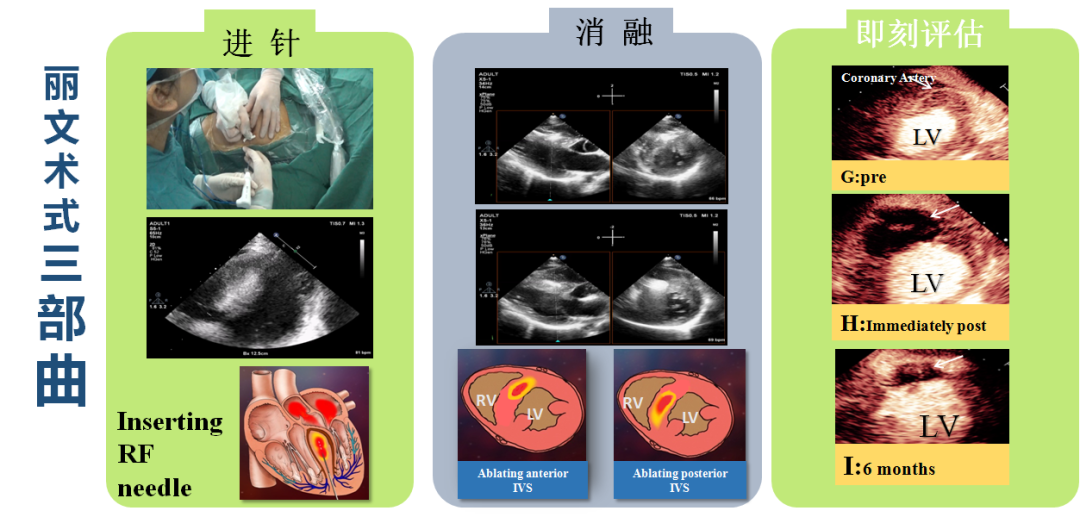

Liwen术式病例介绍

|作者:李静 刘丽文

|单位:空军(第四)军医大学西京医院